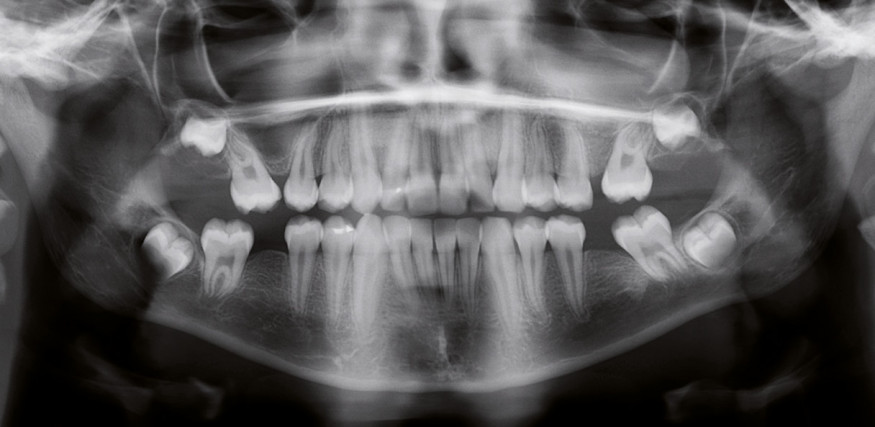

La radiographie panoramique (fig. 3a) montre l’inclinaison corono-mésiale de 17,27 et 37 et la présence des germes des quatre dents de sagesse.